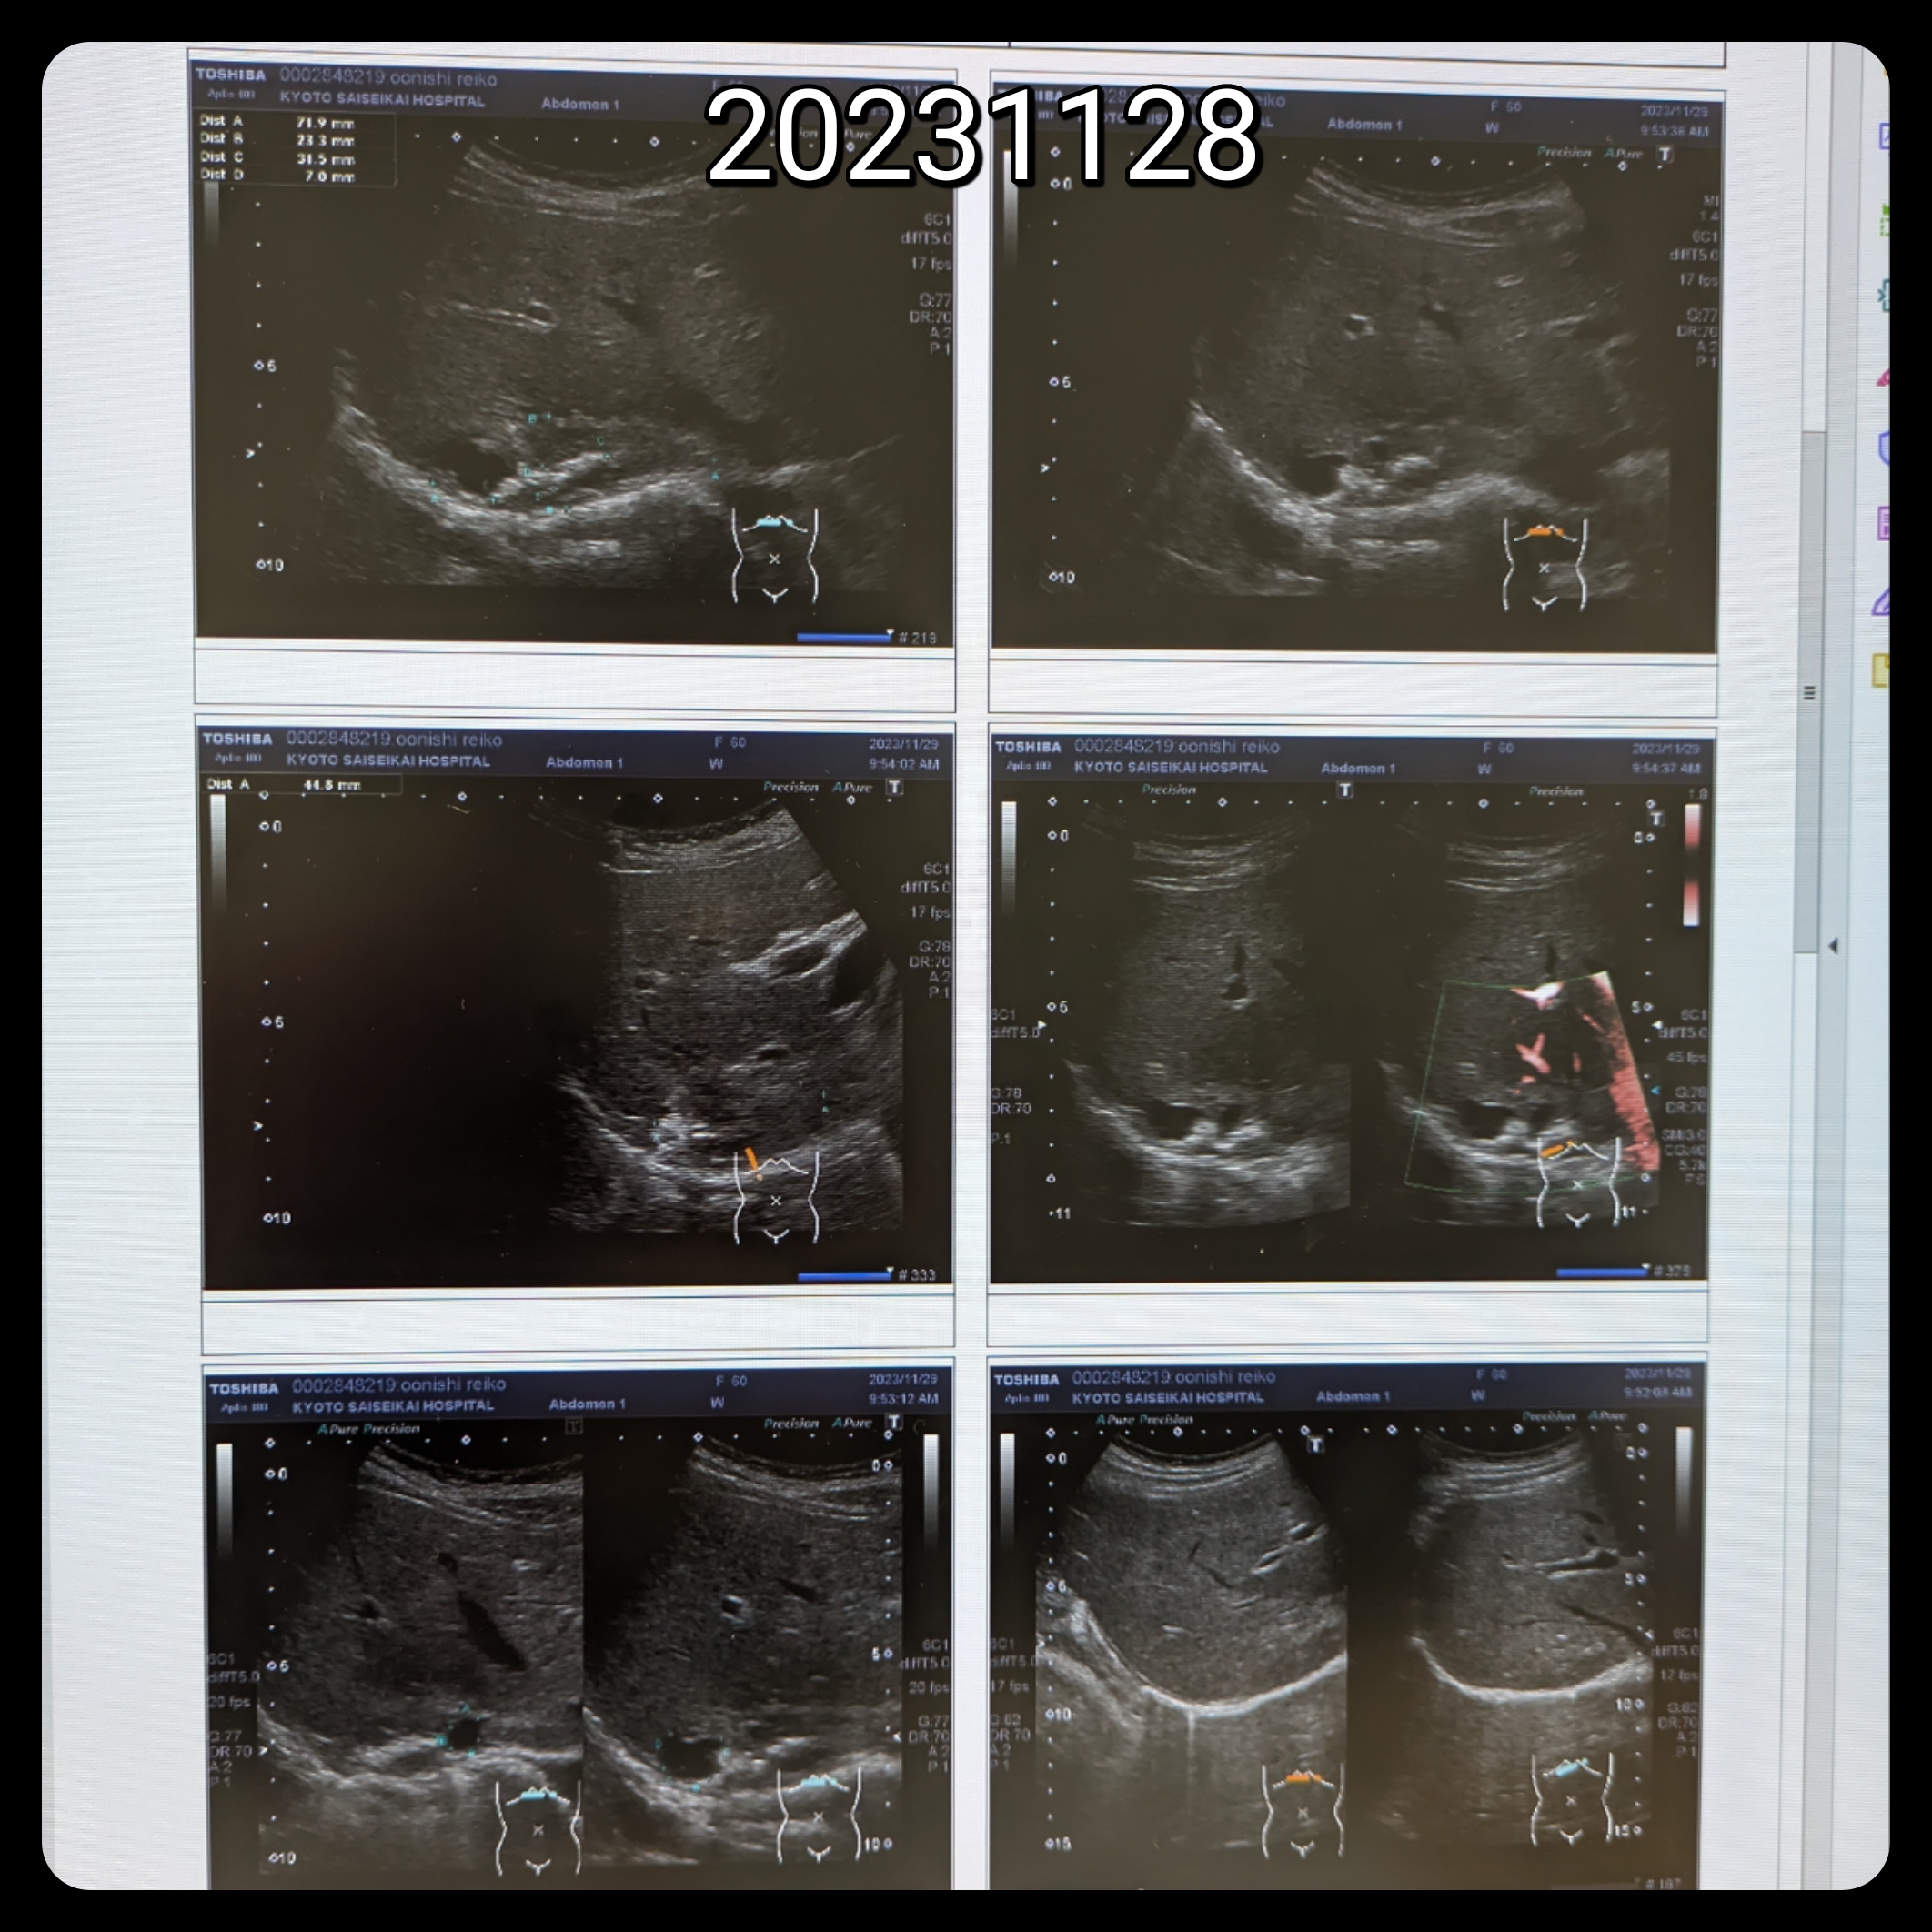

2023.11.30

癌告知はない!肝嚢胞経過観察

20231129↓

3月1日肝嚢胞エタノール注入手術

肝嚢胞は小さくなったけど

肝臓の様子を

画像で列べると

本当に小さくなりましたよね☺